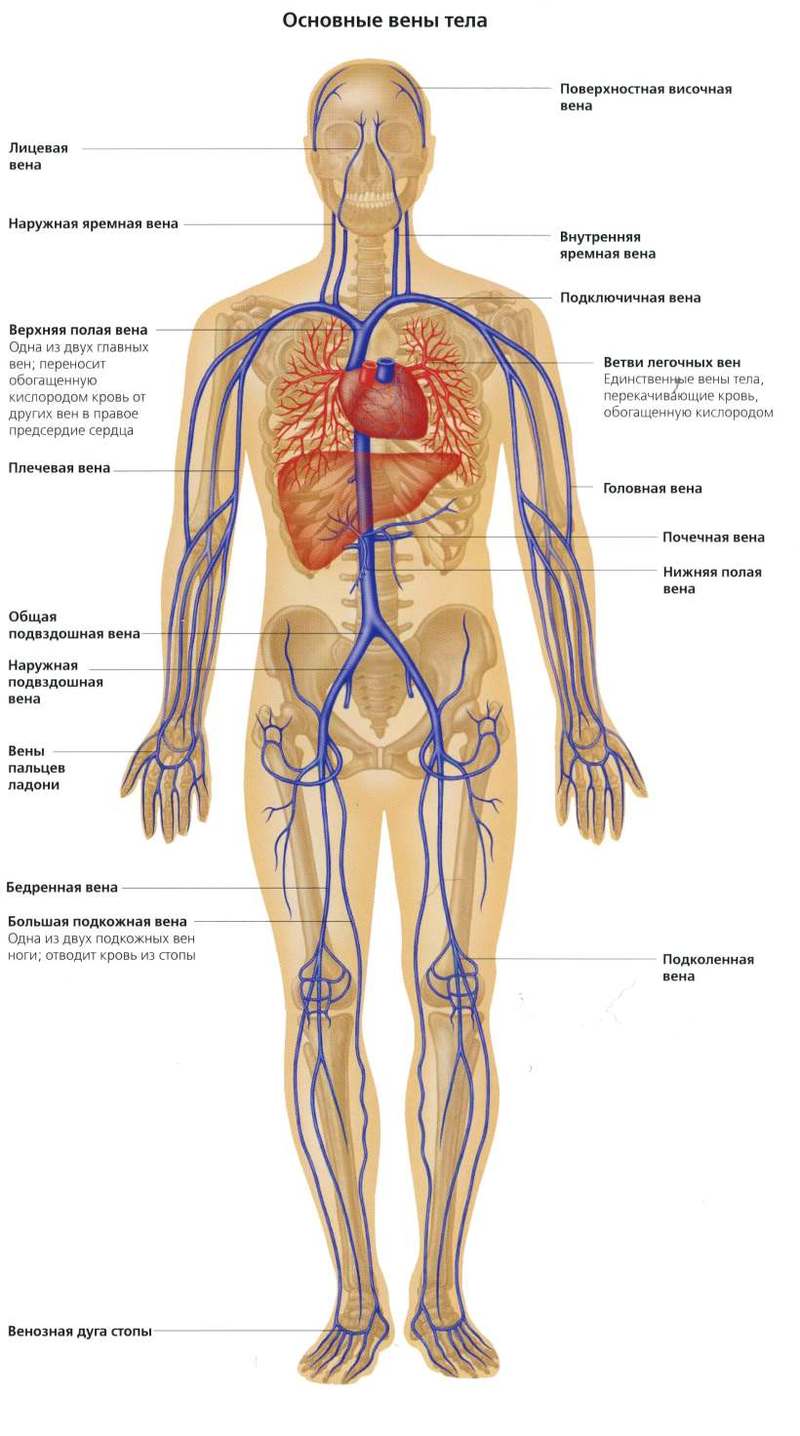

Анатомия человека: кровеносная система и её связь со скелетом

Раздел: Моменты озарения